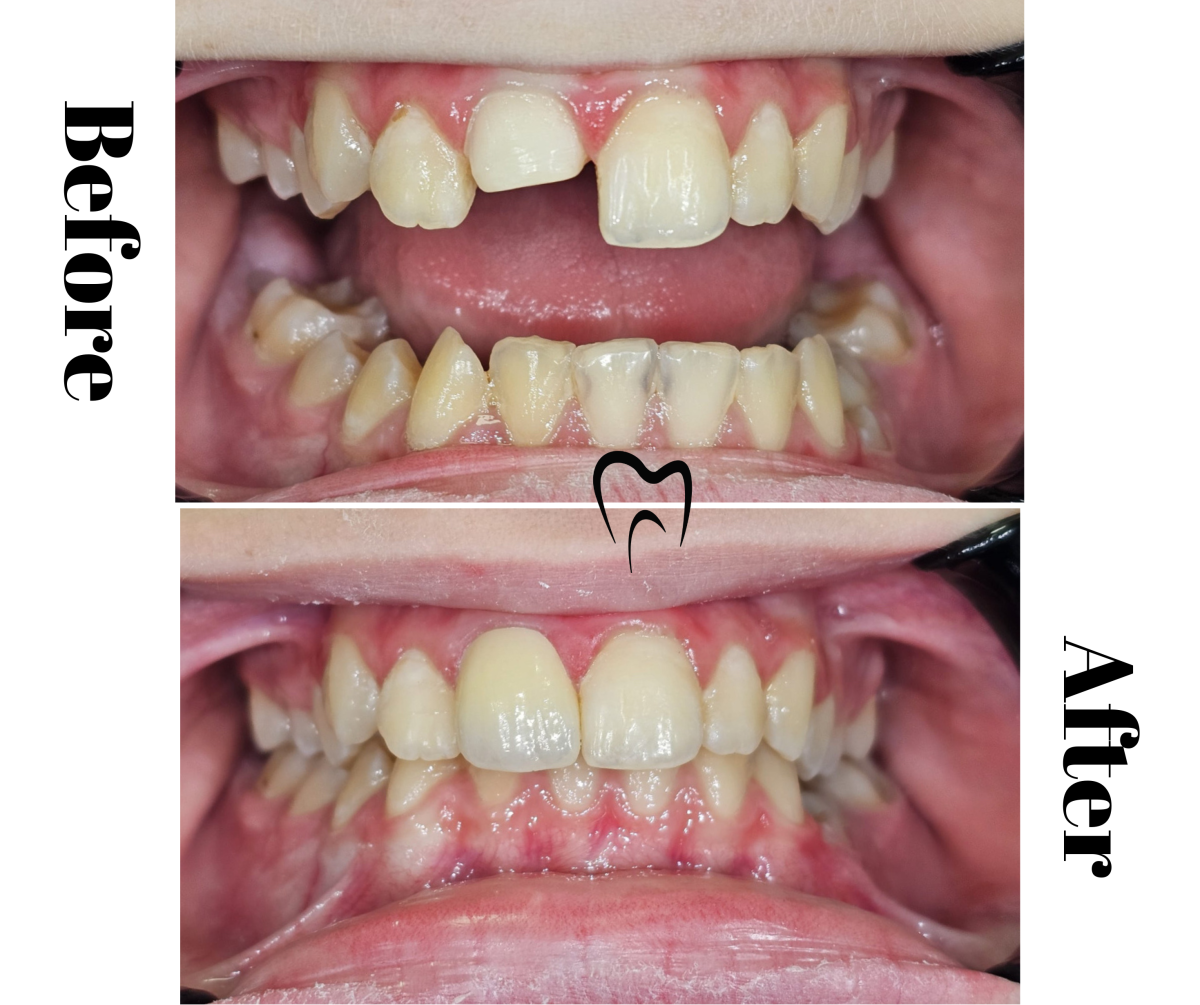

Extracție și aparat ortodontic

Detalii caz